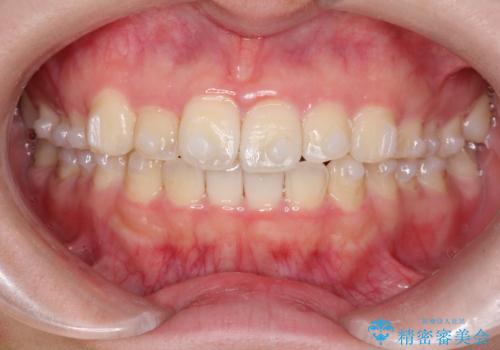

【インビザライン】前歯の凸凹をなおしたい

- 前歯のガタガタを主訴に来院されました。

インビザラインで綺麗な歯並びになり、患者さんには大変満足していただきました。